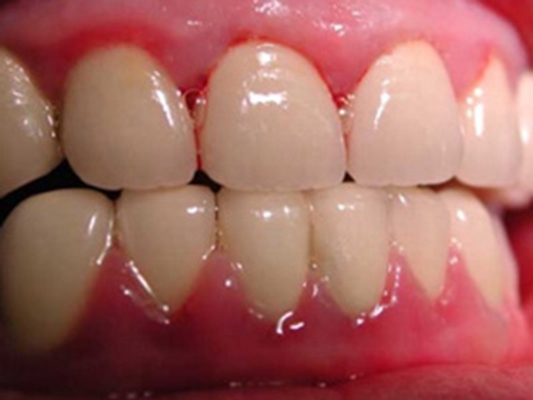

牙周袋 (9)